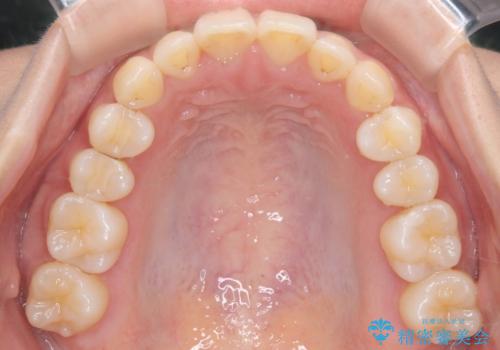

ディープバイト改善のためのインビザライン治療

- 患者様は、全体的な歯列のガタガタとディープバイト(深い噛み合わせ)を主訴として来院されました。診断の結果、ディープバイトを改善するためには、歯列全体の拡大が必要であると判断しました。治療には、透明なマウスピース型矯正装置「インビザライン」を使用し、歯を適切に拡大しながら歯並びを整える計画を立てました。治療期間はおおよそ2年を見込んで進め、最終的に見た目にも大きく変化をもたらすことを目指しました。

ディープバイトの治療には、奥歯の高さや前歯の位置に対する繊細な調整が必要です。本症例では、インビザラインによる歯列拡大を行うことで、噛み合わせを改善し、歯並び全体を整えました。治療過程では、歯間のスペースを確保するため、IPR(インタープロキシマルリダクション)を適宜行い、無理なく歯列の調整を行いました。治療後は、歯並びが大きく改善され、患者様の見た目にも大きな変化が現れました。インビザラインは透明で目立たず、治療中の見た目を気にされる患者様にも配慮した治療法です。